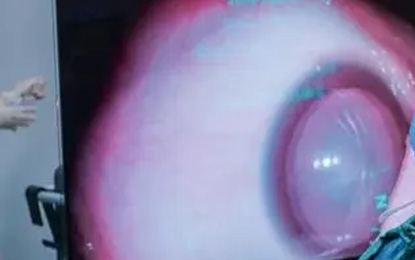

白内障手术是眼科领域中最古老和最常见的手术之一。白内障是指眼睛晶状体变得浑浊,导致视力模糊或丧失。随着医学技术的发展,白内障手术已经从一种风险较高的治疗手段演变为一种安全有效的方法,极大地改善了患者的生活质量。